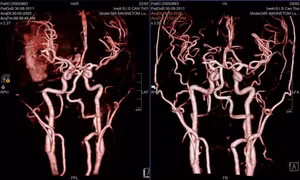

Ngay trong đêm, bệnh nhân được chuyển đến Bệnh viện Quân y 175 cấp cứu. Tại đây, các bác sĩ chẩn đoán người bệnh bị đột quỵ nhồi máu não cấp tính bán cầu trái giờ thứ 3 do thuyên tắc mỡ - biến chứng sau thủ thuật bơm mỡ tự thân vùng thái dương.

Sau hai ngày điều trị, tình trạng phù não diễn tiến nặng. Hình ảnh CT sọ não cho thấy, người bệnh bị nhồi máu diện rộng bán cầu não bên trái gây đẩy lệch đường giữa của bộ não. Sau hội chẩn, ê kíp các bác sĩ chuyên khoa sọ não đã quyết định mổ mở sọ giải áp cấp cứu.

Trong quá trình phẫu thuật, các bác sĩ ghi nhận động mạch thái dương nông nhánh trán ở vùng đỉnh đã bị tắc nghẽn, màu xanh đen, không còn mạch đập. Kết quả giải phẫu bệnh xác định lòng động mạch chứa đầy tế bào mỡ, thành mạch không có dấu hiệu xơ vữa, phù hợp với chẩn đoán thuyên tắc mỡ.